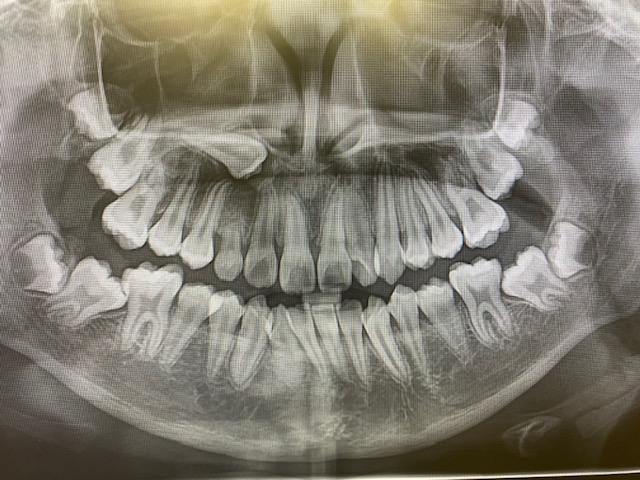

② レントゲン(正面セファロ・側面セファロ・パノラマ)

(👆 当院設置のCTスキャン画像)